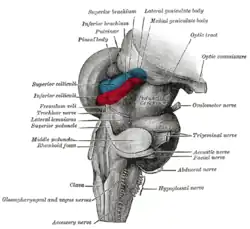

The principal regions of the midbrain are the tectum, the cerebral aqueduct, tegmentum, and the cerebral peduncles. Rostrally the midbrain adjoins the diencephalon (thalamus, hypothalamus, etc.), while caudally it adjoins the hindbrain (pons, medulla and cerebellum).[5] In the rostral direction, the midbrain noticeably splays laterally.

The corpora quadrigemina are four mounds, called colliculi, in two pairs – a superior and an inferior pair, on the surface of the tectum. The superior colliculi process some visual information, aid the decussation of several fibres of the optic nerve (some fibres remain ipsilateral), and are involved with saccadic eye movements. The tectospinal tract connects the superior colliculi to the cervical nerves of the neck, and co-ordinates head and eye movements. Each superior colliculus also sends information to the corresponding lateral geniculate nucleus, with which it is directly connected. The homologous structure to the superior colliculus in non mammalian vertebrates including fish and amphibians, is called the optic tectum; in those animals, the optic tectum integrates sensory information from the eyes and certain auditory reflexes.[7][8]

The inferior colliculi – located just above the trochlear nerve – process certain auditory information. Each inferior colliculus sends information to the corresponding medial geniculate nucleus, with which it is directly connected.

The nuclei of two pairs of cranial nerves are similarly located at the ventral side of the periaqueductal grey – the pair of oculomotor nuclei (which control the eyelid, and most eye movements) is located at the level of the superior colliculus,[10] while the pair of trochlear nuclei (which helps focus vision on more proximal objects) is located caudally to that, at the level of the inferior colliculus, immediately lateral to the dorsal raphe nucleus.[9] The oculomotor nerve emerges from the nucleus by traversing the ventral width of the tegmentum, while the trochlear nerve emerges via the tectum, just below the inferior colliculus itself; the trochlear is the only cranial nerve to exit the brainstem dorsally. The Edinger-Westphal nucleus (which controls the shape of the lens and size of the pupil) is located between the oculomotor nucleus and the cerebral aqueduct.[9]